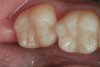

4. A post-polish view of the distal occlusal bulk-filled composite (Beautifil-Bulk Restorative, Shofu) on tooth No. 19. Note the luster as a result of nanofilled composite technology and the chameleon effect that blends the restoration with the tooth surface.

Figure 4